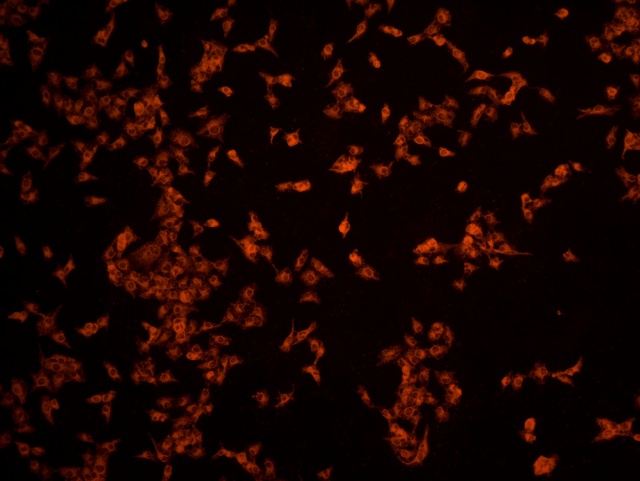

南華大學(xué)在生物醫(yī)學(xué)研究領(lǐng)域一直走在學(xué)術(shù)前沿,近日,該校引進(jìn)Mshot明美的倒置熒光顯微鏡MF52-N,搭配顯微鏡相機(jī)MSX2,為細(xì)胞切片標(biāo)本的研究提供了強(qiáng)大的技術(shù)支持,進(jìn)一步提升了科研實力。

MF52-N倒置熒光顯微鏡以其數(shù)顯LED熒光模塊和深度優(yōu)化的光路設(shè)計,成為細(xì)胞切片觀察的理想選擇。其簡單易用的熒光激發(fā)操作,大大降低了實驗難度,提升了工作效率。同時,該顯微鏡還能提供高質(zhì)量的相襯、熒光和明場成像,確保科研人員能夠捕捉到細(xì)胞切片的每一個細(xì)節(jié)。

在南華大學(xué)的實驗室中,科研人員正借助這套先進(jìn)的顯微系統(tǒng),對細(xì)胞切片標(biāo)本進(jìn)行深入探索。

此外,MSX2顯微鏡相機(jī)的加入,更是如虎添翼。這款相機(jī)以其高分辨率和敏銳的圖像捕捉能力,記錄了實驗過程中的每一個重要瞬間,為數(shù)據(jù)分析與論文發(fā)表提供了有力支持。